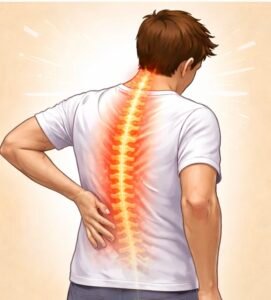

Back Pain

Back pain is one of the most common causes of disability.

It can occur due to disc problems, muscle strain, facet joint arthritis,

or nerve compression.Modern interventional pain treatments such as targeted injections,

radiofrequency procedures, and image-guided therapies can reduce pain

and improve mobility without major surgery.